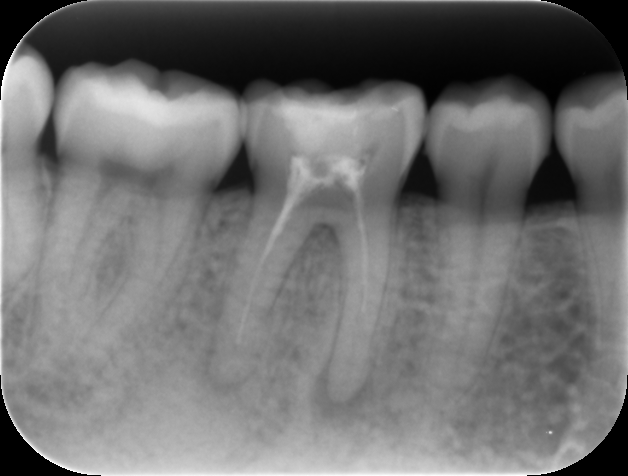

再根管治療12か月後のレントゲンおよびCT画像です。根尖病変は消失し、歯槽骨は完全な再生を認め治癒しています。